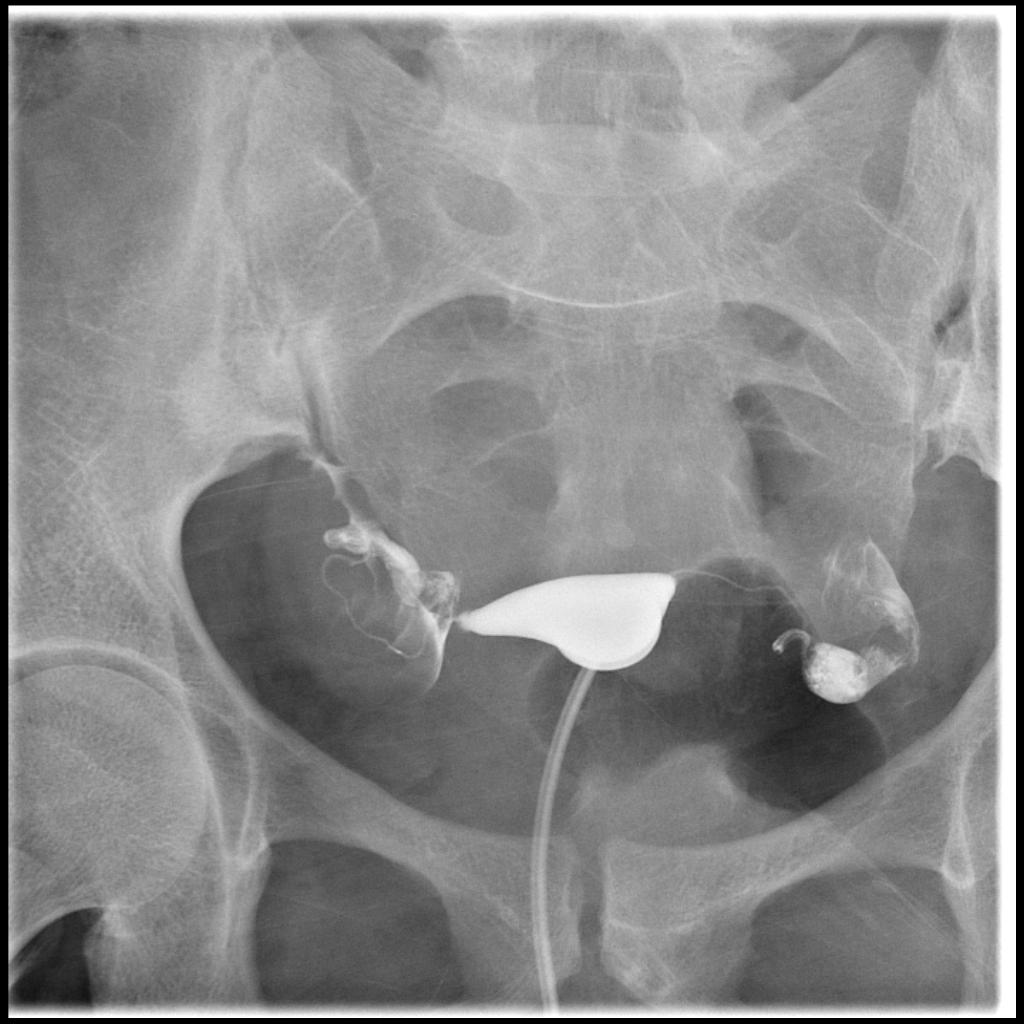

This examination is usually done on an outpatient basis. The patient is made to lie on their back with bent knees on an X-ray table like a Gynaecological exam. The speculum is inserted into the vagina to look the cervix and it is cleaned and a catheter is inserted into the Cervix. The catheter is connected with the syringe which contains the dye. Then the dye is pushed into the Uterus. If the tubes are patent, the dye will be released into the other ends of the tube and the Fluoroscopic images are taken immediately after the dye is pushed into the Uterus.

In some cases, if certain abnormalities are encountered, the patient will be asked to take rest and wait up to 30 minutes, so that a delayed image can be obtained. This delayed image may provide clues to a patient's condition that the original images with contrast material do not. On occasion, an X-ray will be taken on the next day to ensure that there is no scarring surrounding the ovaries. When the procedure is complete, the catheter will be removed and the patient will be allowed to sit up. Other abnormalities, if any, are clearly visible from the X-ray images.